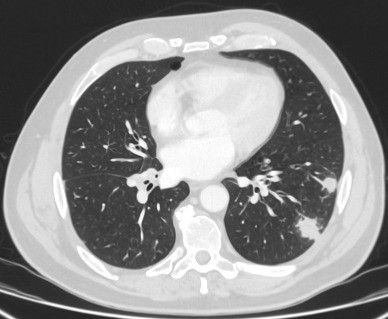

[Figure caption and citation for the preceding image starts]: Computed tomography (CT) showing a right upper lobe apical solid nodule with a surrounding ‘ground glass’ halo, in a patient with seropositive rheumatoid arthritis on methotrexate. Other similar nodules were seen throughout both lungs, and remain stable for >2 years, consistent with inflammatory benign rheumatoid nodulesFrom the collection of Dr George Tsaknis, MD, PhD, FRCP(London), MRQA, MAcadMEd, PGCert; used with permission [Citation ends].